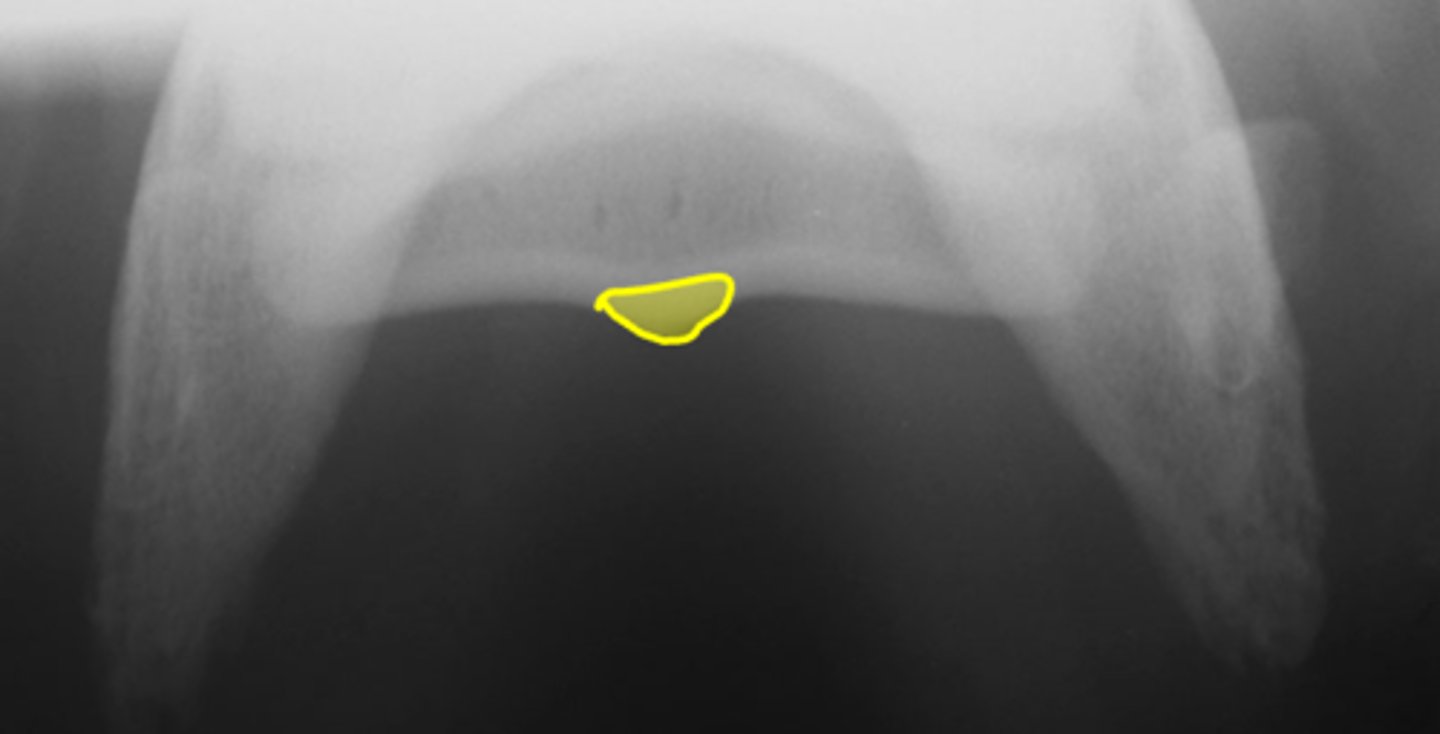

Navicular bone

Flexor cortex

Navicular bone

Proximal border of navicular bone

Distal border of navicular bone

Synovial invaginations

Flexor skyline

What view is this?

1. Flexor surface

2. Corticomedullary distinction

3. Number of synovial invaginations

What is the flexor skyline used to evaluate?

Navicular bone

Articular surface of navicular bone

Flexor surface of navicular bone

Sagittal ridge

Synovial invaginations